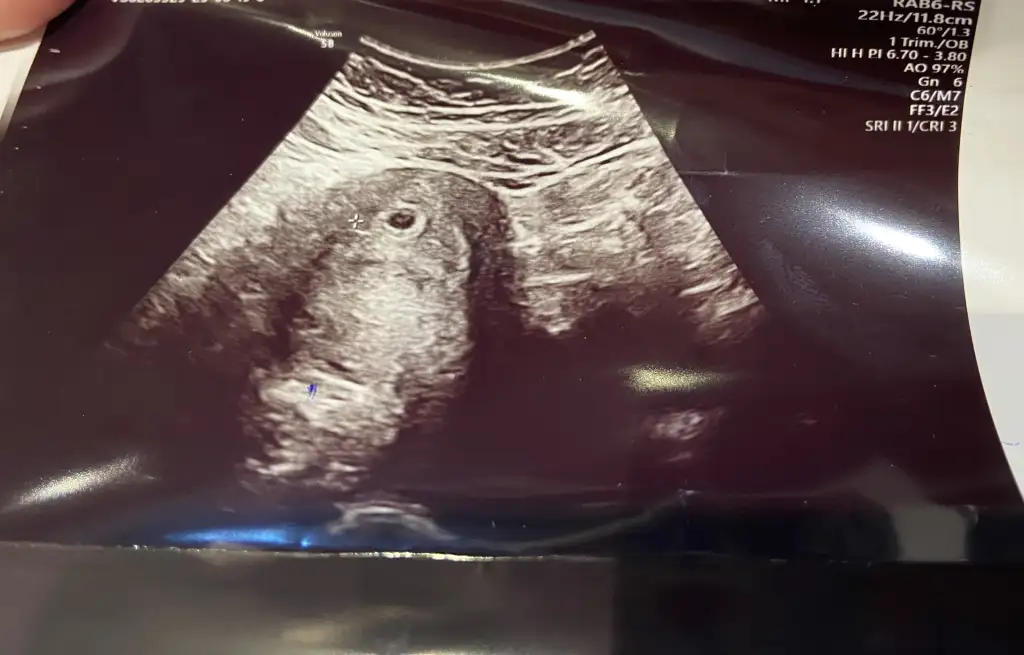

Kızlaaarrrr kese göründü 😍😍 bakar mısınız yolla saç da var yani sağlıklıdır dimiiiii 5+2 bugün 🥹🥹

Ya kafam şeye takıldı. Bugün kese boyu 4 mm on gün sonra 14 mm olur kalp atışı da 18 19 mm den sonra duyuluyor deniliyor o zaman ben on gün sonra duyamayacak mıyım korkuyorum şu an 😞😞 senin kese gördüğün kese boyutu ve kalp atışı duyduğunda kaçtı acaba

5+4 te 11 mm kese. 6+4 4 mm kalp atışı aldık ama vajinal duyuldu. Canım sen şimdiden dert etme 6+4 duyulmayabilir. İlk gebeliğimde 7+4 te anca duymuştum

Ayy inşallah ya kesem haftaya 14 mm falan olur kalp atışını keseniz kaç mm ken duydunuz kese 20 üstü olması gerek aslında kalp atımı için ya duyamazsam 😔😔 çok stresli ve üzgünüm şu an